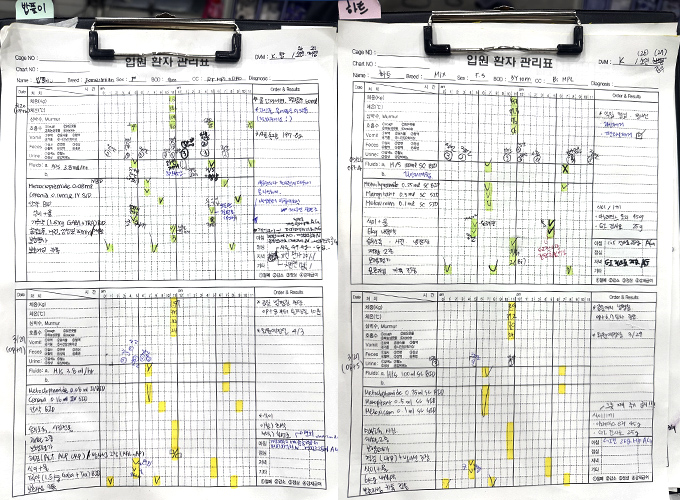

수술 후 회복까지 책임집니다

수술 후 관리

입원이 필요한 경우, 베테랑 의료진의 24시간 밀착 입원 관리가 진행됩니다.

꼼꼼한 환자 차트관리

매일 옥상 정원 산책

입원 중 재활치료 가능